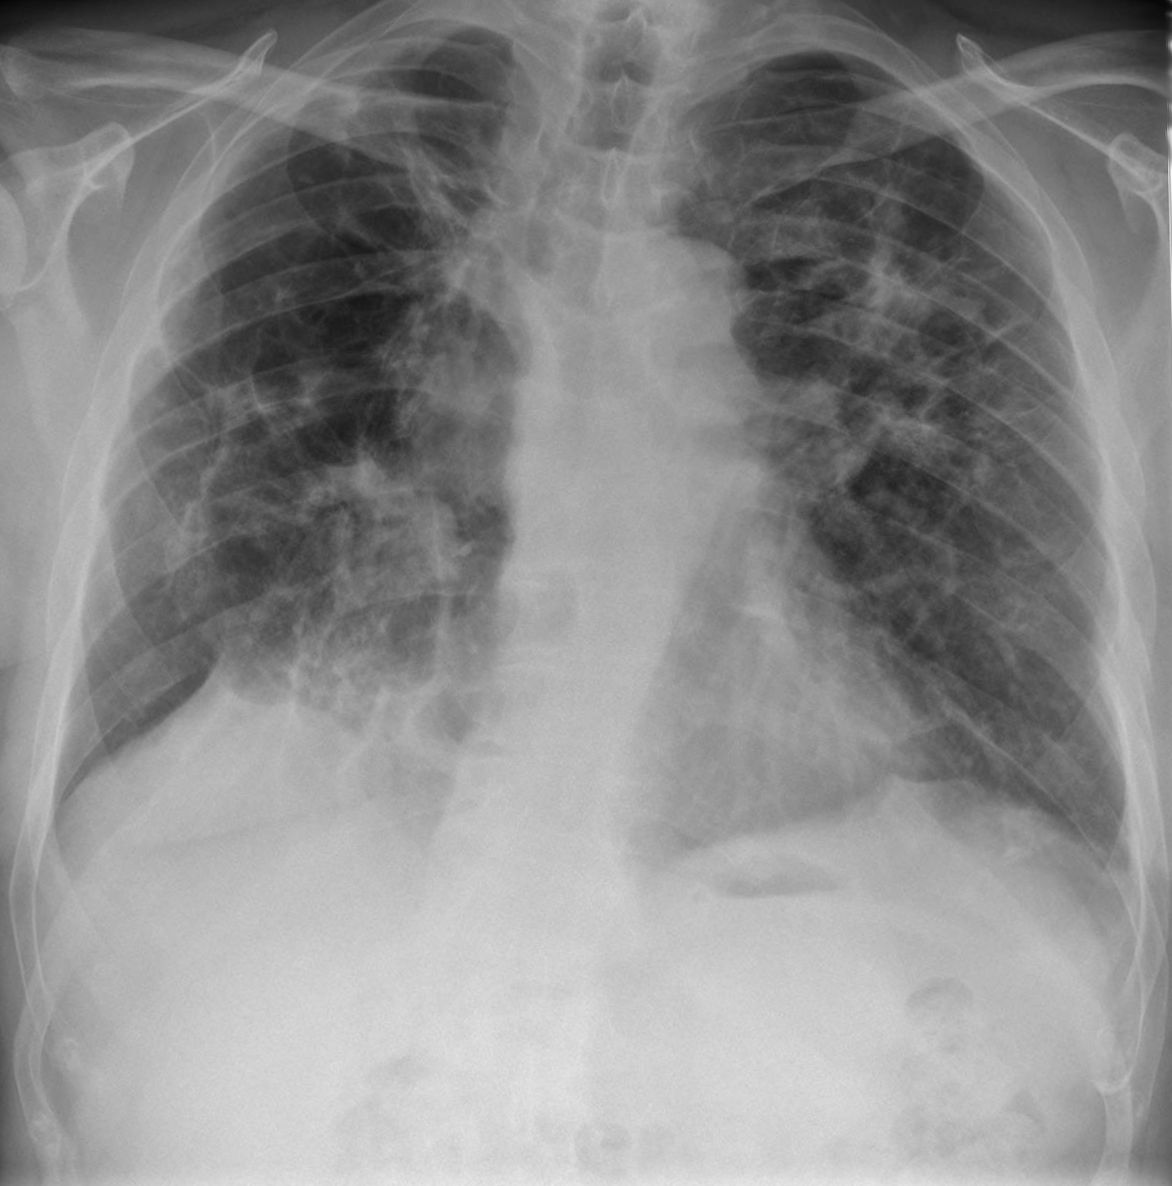

In Deutschland leben etwa 32.000 bis 40.000 Menschen mit einer Sarkoidose. Diese Erkrankung macht sich meist durch knotenförmige Gewebeveränderungen bemerkbar und betrifft vor allem die Lungen. Mediziner unterscheiden zwischen akuter oder chronischer Sarkoidose, die Ursache ist jedoch in beiden Fällen ungeklärt.

Sarkoidose ist eine entzündliche Erkrankung, die in zwei Formen auftreten kann. Die chronische Sarkoidose ist mit etwa 95 Prozent die häufigere. Rund die Hälfte aller Fälle bleibt symptomfrei. Die akute Sarkoidose, das sogenannte Löfgren-Syndrom, tritt sehr plötzlich auf und macht sich unter anderem durch Hautveränderungen und Lymphknotenschwellungen bemerkbar. Was die Erkrankung verursacht, ist bisher unbekannt.